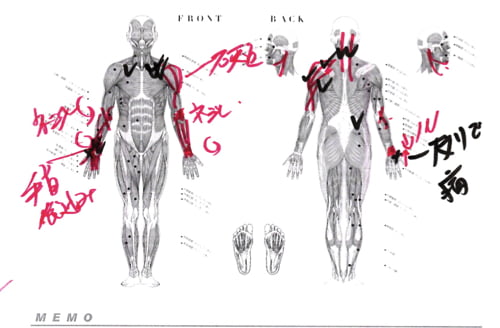

実際にお身体の状態を診させて頂くとこんな感じでした。

赤い線は筋肉や腱の硬直や捩れ。✔は痛みのある場所。

四十肩は多くの場合、肩そのもの、関節や骨に異常はありません。

四十肩を引き起こし大きな原因の1つは手首のねじれ。

それは指の酷使から来ます。

それらが硬直や捩れを起こすと手首や肘もネジレてしまいます。

肘がネジレるとこんな感じで繋がっている肩や肩甲骨の位置にずれが生じます。

今回の四十肩の原因は手首と肘のネジレが根本原因でした。